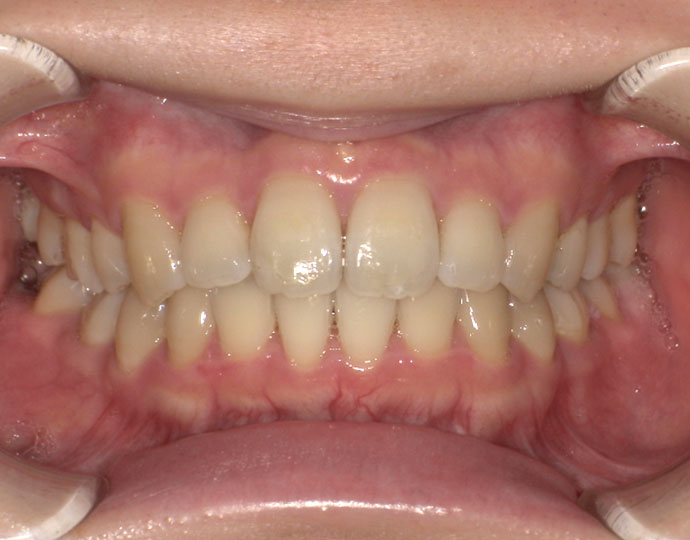

ワイヤー治療 叢生+上顎前突不正咬合 治療例

治療後

| 診断 | 叢生歯列を伴う上顎前突不正咬合 |

| 治療方針 | 上顎左右第一小臼歯、下顎左右第二小臼歯の抜歯 |

| 治療に使用した装置 | セルフライゲーションブラケット インプラントアンカースクリュー×2 |

| 治療期間 | 2年6カ月 |

| 治療回数 | 24回 |

| 治療費(自費診療) | 880,000円(税込み) |